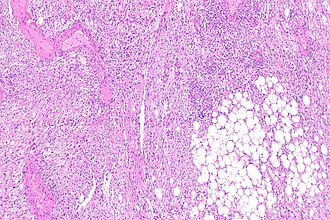

Micrograph showing a renal angiomyolipoma, as may be seen in tuberous sclerosis. H&E stain. (WC/KGH)

- Renal angiomyolipoma.